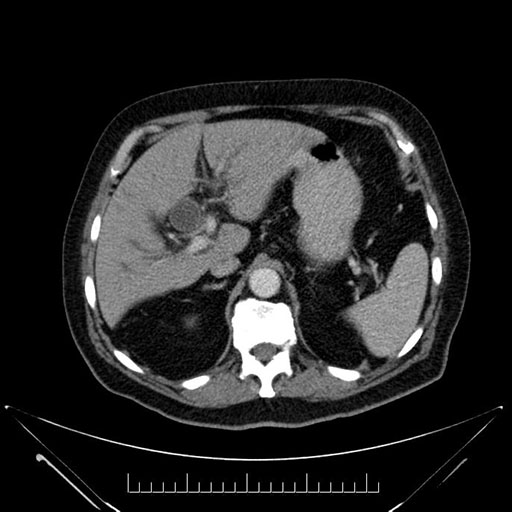

Imaging Analysis

Look through the patient's CT scan to identify any areas of concern for the necessary procedure.

Based on your CT findings, which issue(s) would give reason for "planned slowing down moment(s)" in this case?